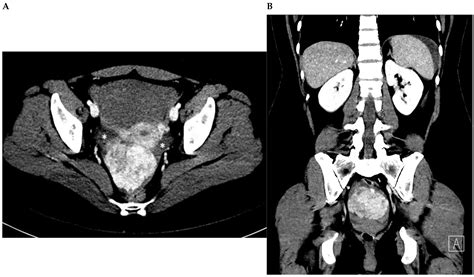

Computed Tomography (CT) Scan Provides detailed images of the blood vessels, allowing for the detection of aneurysms, dissections, or other abnormalities.